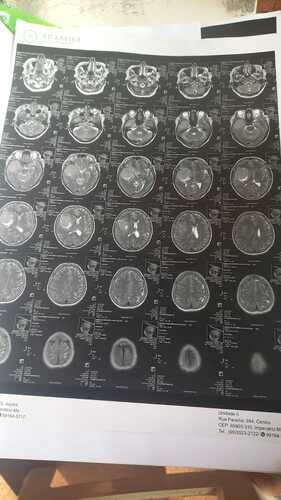

Recentemente, Maria do Socorro recebeu o diagnóstico devastador de um tumor na cabeça. Esta notícia abalou não só ela, mas todos nós que a amamos e admiramos. No entanto, Maria do Socorro é uma lutadora e está determinada a vencer esse tumor.